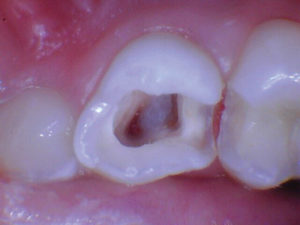

Figura 3. Después de quitar el techo de la cámara pulpar. |

Figura 4. Después de excavar el tejido pulpar en los orificios del canal, se utilizó una prenda de algodón seco para evaluar la salud de la pulpa mediante la aplicación de hemostasia por presión. |

Figura 5. Esta pulpa exhibió una pulpa radicular sana como lo demuestra el sangrado fácilmente controlado. |